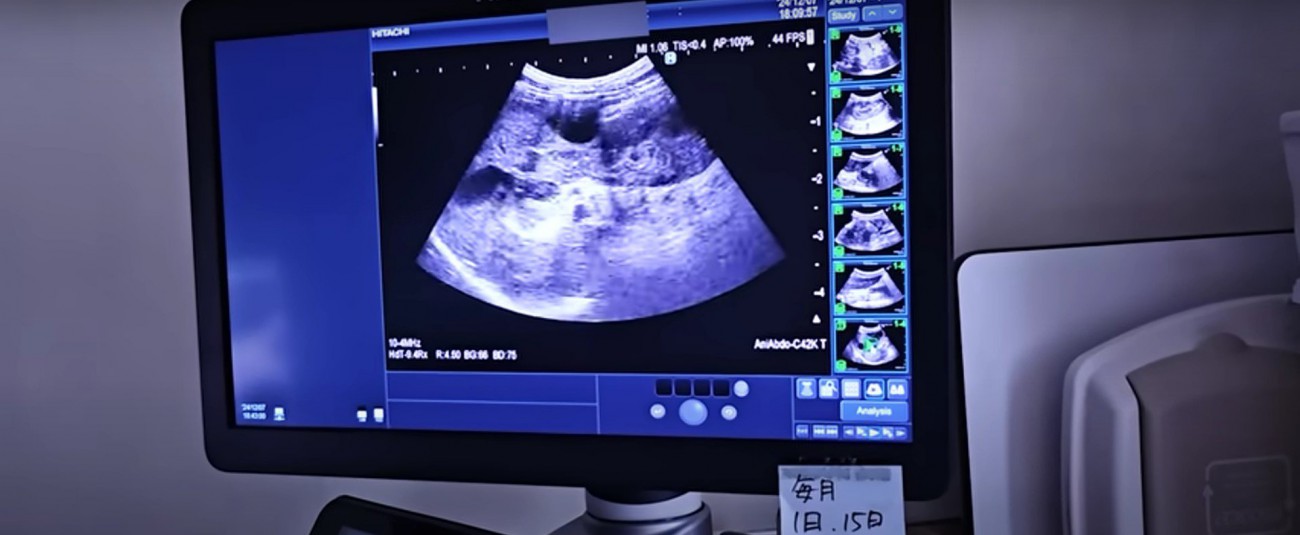

エコー検査を行った結果、ビスコちゃんには「胆泥症」の様な症状があったのだとか。胆泥症は胆汁が濃縮したものが胆のうに溜まる病気のこと。主に高齢の猫や犬に見られる症状で、病院の先生も猫では初めて見るという珍しい症状だといいます。

加えて少量ではあるものの腹水も溜まっていたため、この日は抗生物質や痛み止めなどを入れた皮下点滴だけして翌日まで様子を見ることに。

翌日、朝から入院し静脈点滴や再検査を受けたビスコちゃん。エコー検査の結果は昨日よりは良くなっていたため、対症療法をしながら今後の検査をどうするか考えることになったのだとか。